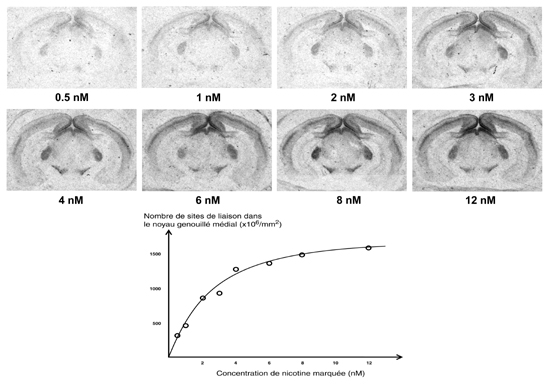

Figure 11.3 : Liaison de différentes concentrations de nicotine tritiée sur des coupes de cerveaux de rat (Bregma -5,3 à -6,3 mm). La courbe représente le signal mesuré dans le noyau genouillé médial du thalamus. Chaque point résulte de la moyenne de mesures effectuées sur plusieurs coupes. La courbe obtenue de cette manière est moins fiable que son équivalent réalisé sur homogénat. En effet le KD résultant peut être influencé par de nombreux paramètres expérimentaux.

saturation de la liaison de nicotine tritiée

En pratique une seule concentration est suffisante pour les études de localisation et les comparaisons simples (par exemple entre un contrôle et un traitement). Le choix de la concentration de ligand à utiliser est fonction de la courbe de saturation. Si la concentration est trop faible, une faible fraction des sites de liaison réellement présents sera révélée. En revanche, si la concentration est trop forte, le marquage sera saturant, et l'on verra tous les sites. Mais on risque d'avoir beaucoup de bruit de fond, voire de révéler des sites de liaison indésirables de faible affinité. Une concentration possible est 4 x Kd qui révèle 80 % des sites présents.